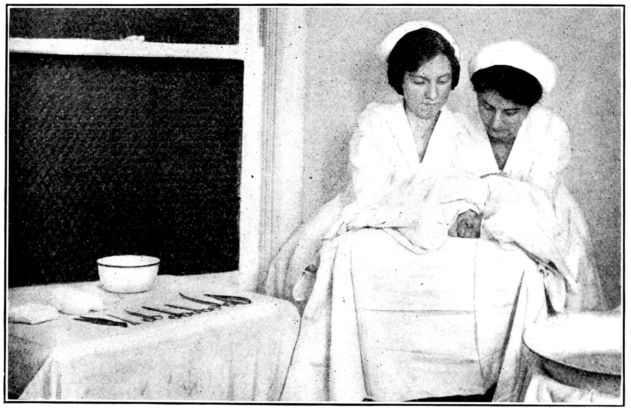

| 155. | Preparation for circumcision | 468 |

| 156. | Baby draped with sterile sheet, in above | 469 |